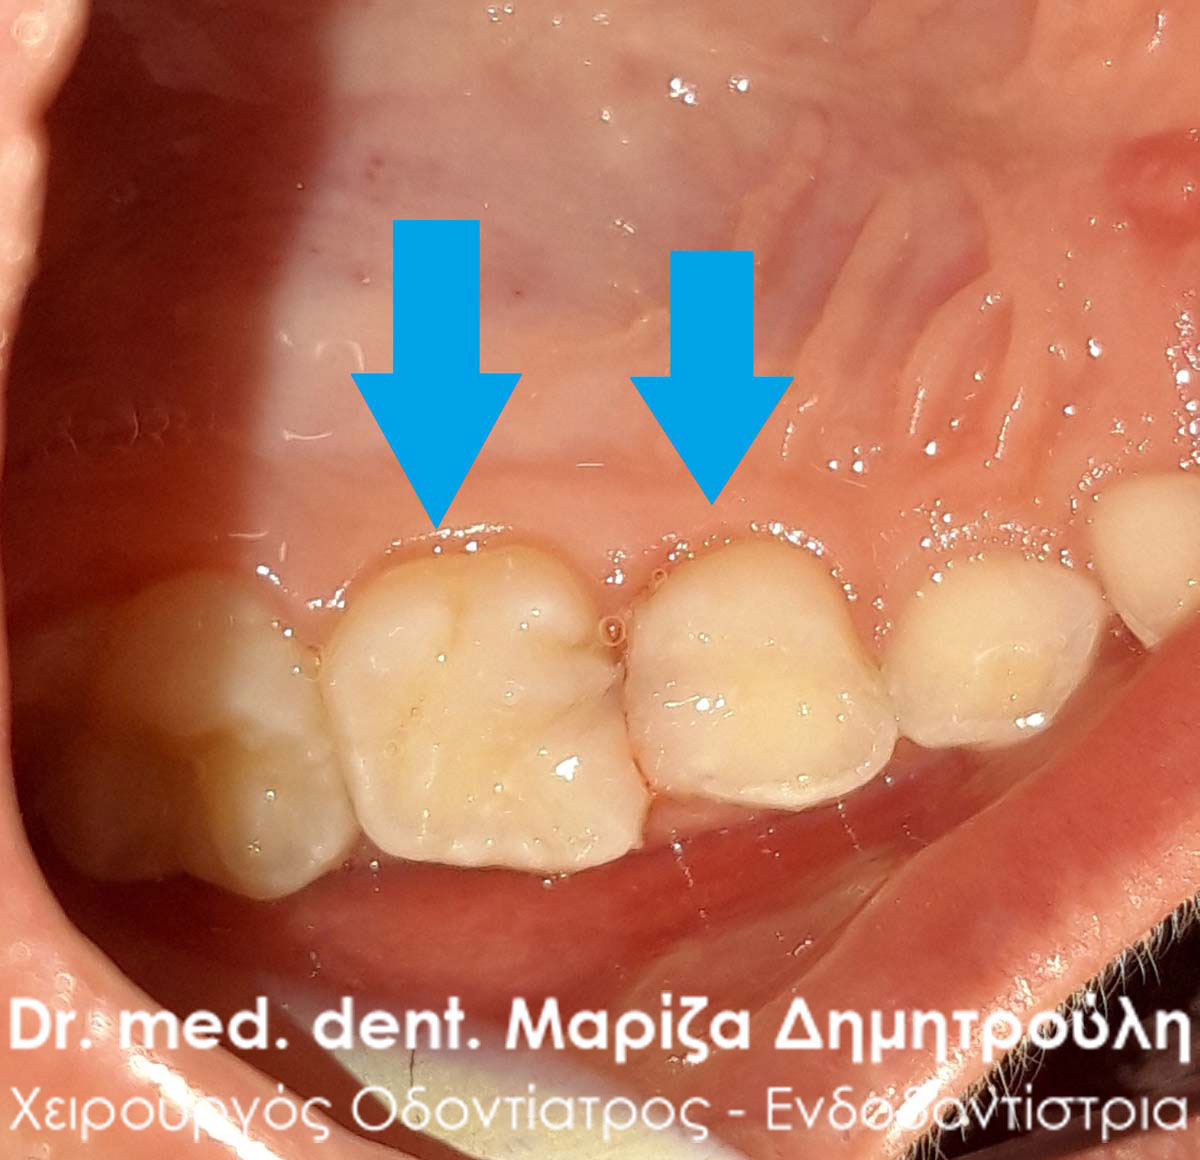

Ο νεαρός πονούσε πάρα πολύ όταν έτρωγε καθώς είχε δύο σχετικά μεγάλες τερηδονικές αλλοιώσεις στους 2 νεογιλούς γομφίους της άνω γνάθου. Τα δόντια αποκαταστάθηκαν με 2 σφραγίσματα ρητίνης στην ίδια συνεδρία.

ΠΡΙΝ

ΜΕΤΑ